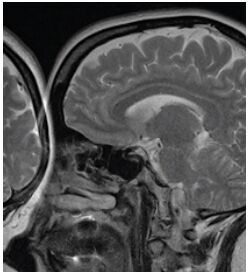

35.下圖箭頭處所指為下列何者?

(A)medial rectus muscle (B)superior ophthalmic vein (C)optic nerve (D)lateral rectus muscle